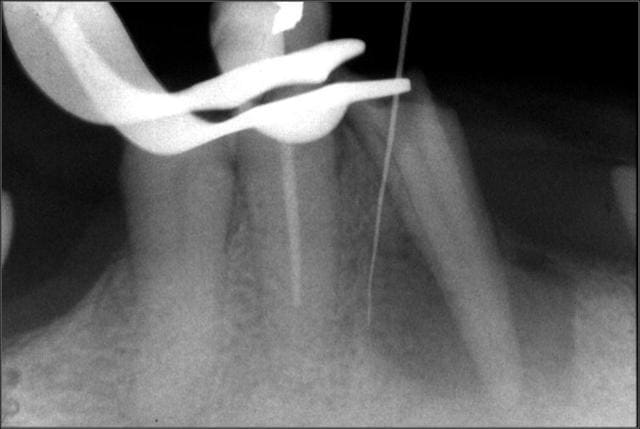

Cas déja posté. F2 neuf cassé dans un canal DL de 36 suite à une petite précipitation à la fin de l'endo.

Dommage car quand on voit la préop et les calcifications, on pouvait se dire que j'avais fait le plus dur.